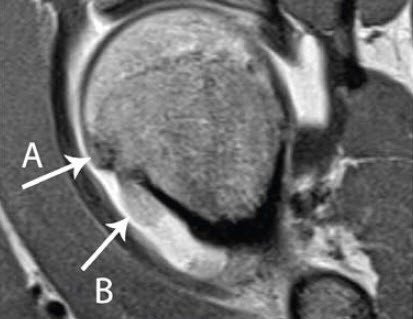

Das Hüftimpingement kann angeboren sein oder im Rahmen einer Entwicklungsstörung des Gelenks entstehen. Die Diagnose ist anhand konventioneller Röntgenaufnahmen nicht immer eindeutig zu stellen. Deswegen erfolgt die definitive Diagnostik meist mittels eines speziellen MRI (mit Kontrastmittel), womit auch Schäden an Knorpel und Labrum gezeigt und quantifiziert werden (Abb.1).

Bei der klinischen Untersuchung des jungen Patienten zeigte sich eine für das FAI typische eingeschränkte Beweglichkeit, und die konventionellen Röntgenbilder wiesen ebenfalls auf ein FAI hin. Ein mitgebrachtes MRI zeigte jedoch eine für ein FAI unüblich stark ausgeprägte Entzündungsreaktion im Knochen, der Gelenkschleimhaut und des Knorpels. Zusätzlich beschrieb der Patient zunehmende Nachtschmerzen, welche in diesem Ausmass beim FAI nicht gesehen werden.

Die ungewöhnliche klinische Präsentation und ein bei uns durchgeführter Aspirin-Test, der eine vollständige Schmerzreduktion zeigte, begründete deshalb den Verdacht auf ein intraartikuläres Osteoid-Osteom (IAOO), welches die Symptome eines FAI nur imitierte und mithilfe einer Computertomografie nachgewiesen wurde. Aufgrund der Lokalisation des IAOO entstand möglicherweise eine Konturveränderung des vorderen Schenkelhals-Oberschenkelkopf-Übergangs, die zu einer Impingement-Situation führte.